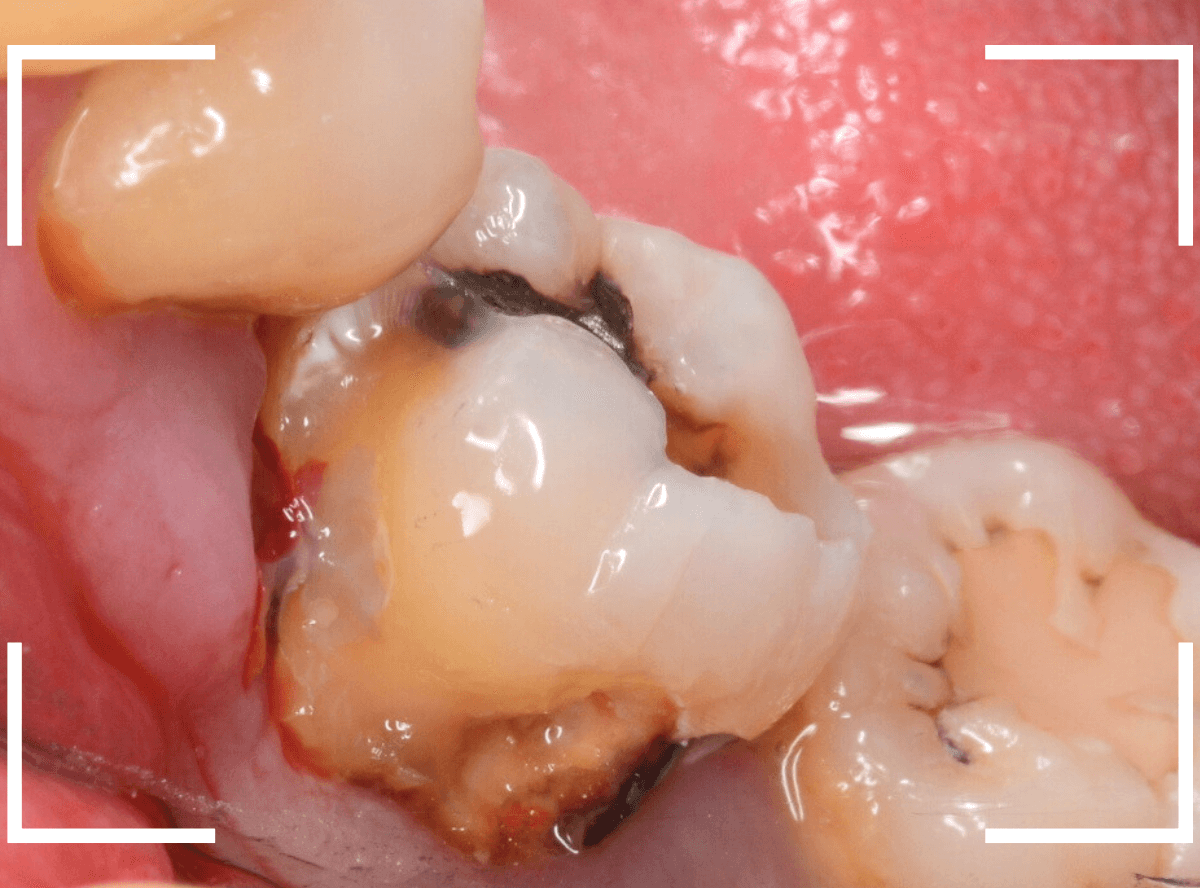

Case.14 CR(コンポジット・レジン)の下の深い虫歯

奥歯で咬んだ時に、痛みを感じるという訴えで来院された患者さんです。

パッと見は特に問題なさそうな状態ですが、大きなレジン治療がしてあり、レジンの奥もボヤっと黒っぽく見えてアヤシイ感じです。

麻酔をして、治療を開始します。

レジンを外すと、中から出血してきました。

これは、歯のスキマに歯肉が入り込んでしまったために起こってしまったものです。

おそらく、随分前から虫歯が進行していたと思われます。

止血しながら、電気メスで歯の中に入り込んだ歯肉を除去します。

虫歯と入り込んだ歯肉でぐちゃぐちゃになっている状態でした。

これでは、痛みが出てもおかしくありません。

慎重に全ての虫歯を除去したところです。

〇部が神経の入り口が見えているところです。

神経を保護する処置をして、しばらく経過観察しますが、痛みが出て神経を除去する必要が出る可能性も高いです。

痛みが出ませんように・・・。